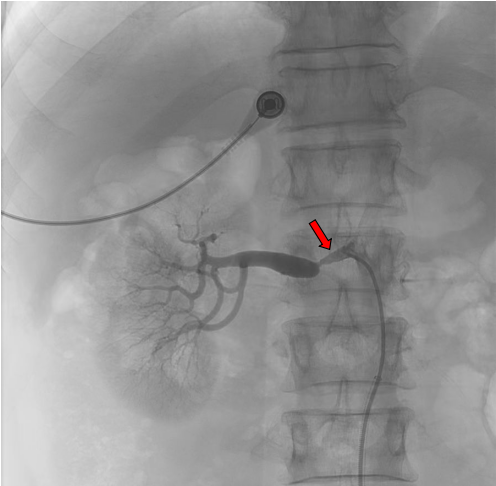

血管CTA图像(红色标记为右肾动脉狭窄部位)

患者于5年前体检发现高血压。当地诊断为高血压病,口服降压药治疗,血压控制尚好。2年前体检发现腹主动脉硬化,并溃疡形成,定期复查。2024年3月在本院门诊行CTA检查时发现右肾动脉明显狭窄,右肾灌注减少。